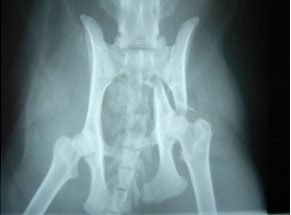

骨盤骨折 : 症例1 | 症例2 | 症例3 | 症例4